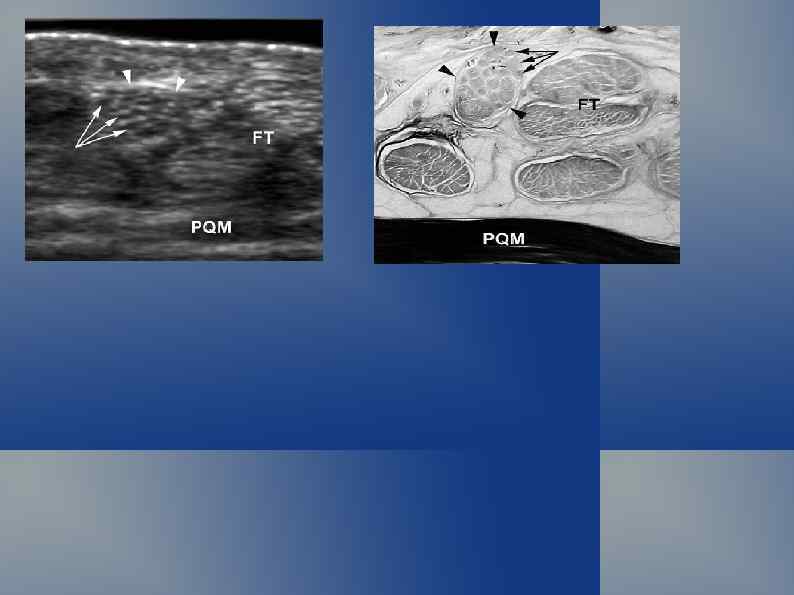

Нормальная ультрасонографическая картина Кожа и подкожная клетчатка

Нормальная ультрасонографическая картина УЗ-сканирование по задней поверхности голени: малая подкожная вена, мелкие подкожные вены, n. suralis